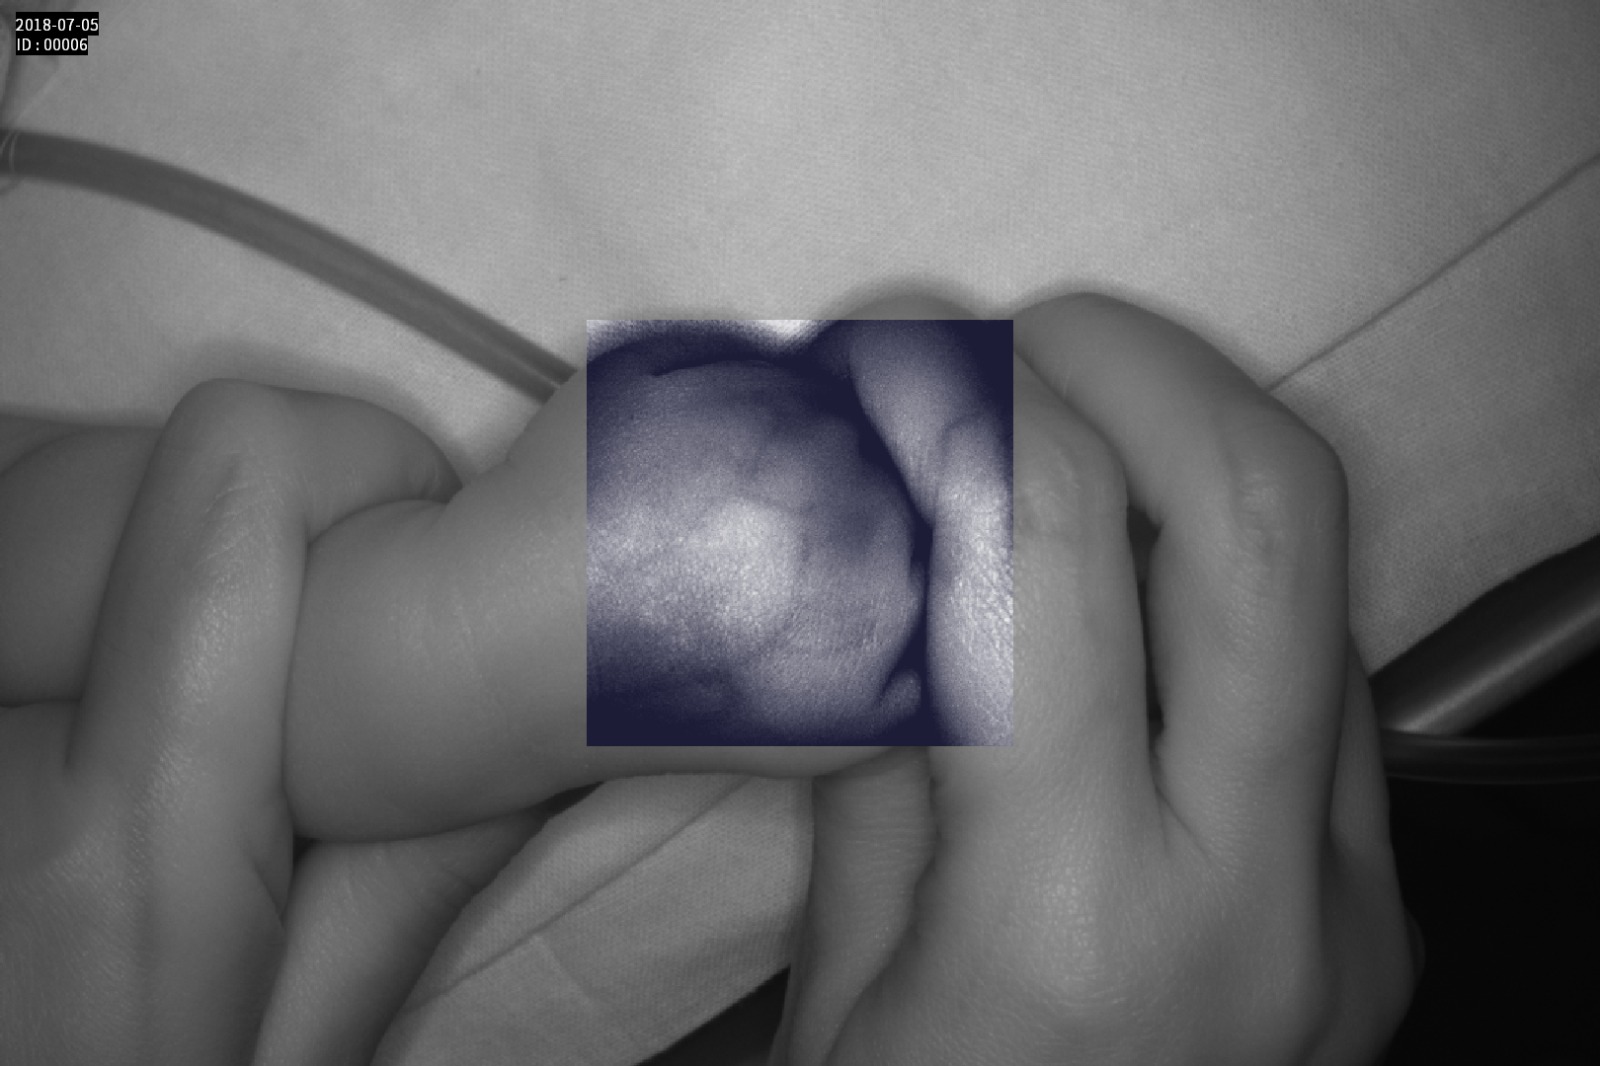

Dispozitiv medical portabil, non-contact, ce ajută la vizualizarea venelor pentru efectuarea puncției venoase, intervențiilor chirurgicale plastice, diagnosticul venelor varicoase.

Grad mare de detecție a venelor greu vizibile până la 10 mm adâncime (inclusiv vene faciale)

Imaginea venelor este proiectată pe monitorul propriu în timp real si ajută la identificarea corectă și precisă

Multiple aplicații de vizualizare vene atât la sugari cât și la pacienții obezi sau în urgențe indiferent de tonul de culoare a pielii